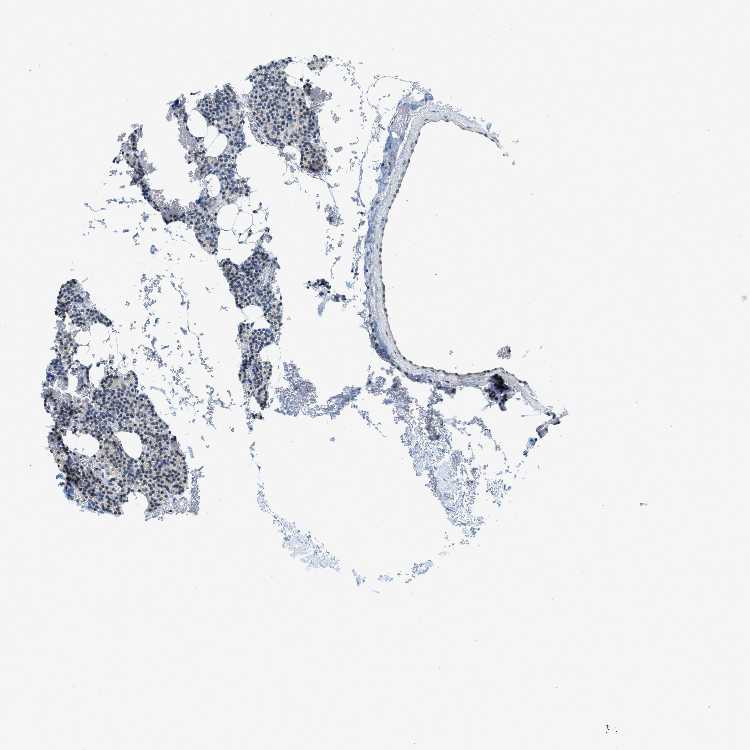

TISSUE PRIMARY DATA PARATHYROID GLAND Show tissue menu

PARATHYROID GLAND - Antibody stainingi

Antibody staining in the annotated cell types in the current human tissue is reported as not detected, low, medium, or high, based on conventional immunohistochemistry profiling in selected tissues. This score is based on the combination of the staining intensity and fraction of stained cells.

Each image is clickable and will lead to virtual microscopy that enables deeper exploration of all samples and also displays staining intensity scores, fraction scores and subcellular localization as well as patient and tissue information for each sample.

Antibody HPA017899

Glandular cells Medium